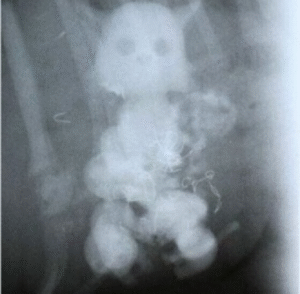

Ao ser admitido no hospital, o paciente passou por exames de imagem que confirmaram o que parecia improvável: a presença de uma boneca alojada internamente. O quadro exigiu avaliação urgente, e os médicos cogitaram realizar uma intervenção cirúrgica para remover o objeto. A equipe médica acompanhou o caso com cautela, temendo possíveis complicações. Contudo, para surpresa de todos, o desfecho foi mais positivo do que se esperava. O idoso conseguiu expelir a boneca de forma natural, sem necessidade de cirurgia, e foi liberado após observação.